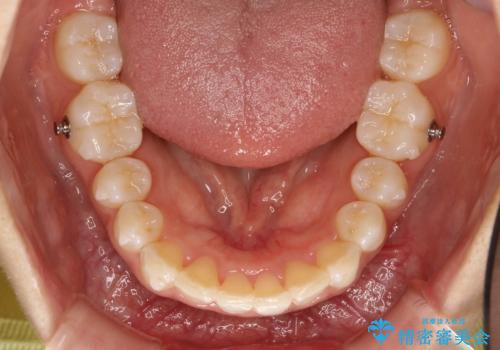

Invisalign インビザラインによる軽度なガタつきの改善

- invisalign full

- 9ヶ月

- 奥歯の位置関係はそこまで大きくいじらず、前歯群のみでガタつきの改善を計画しました

奥歯の位置関係に改善の余地はありますが、機能的に問題のない cusp to fossa の関係で咬めているため、前歯のガタつきを前歯のみで改善するというシンプルな計画で、短期間で治療を終了させました。